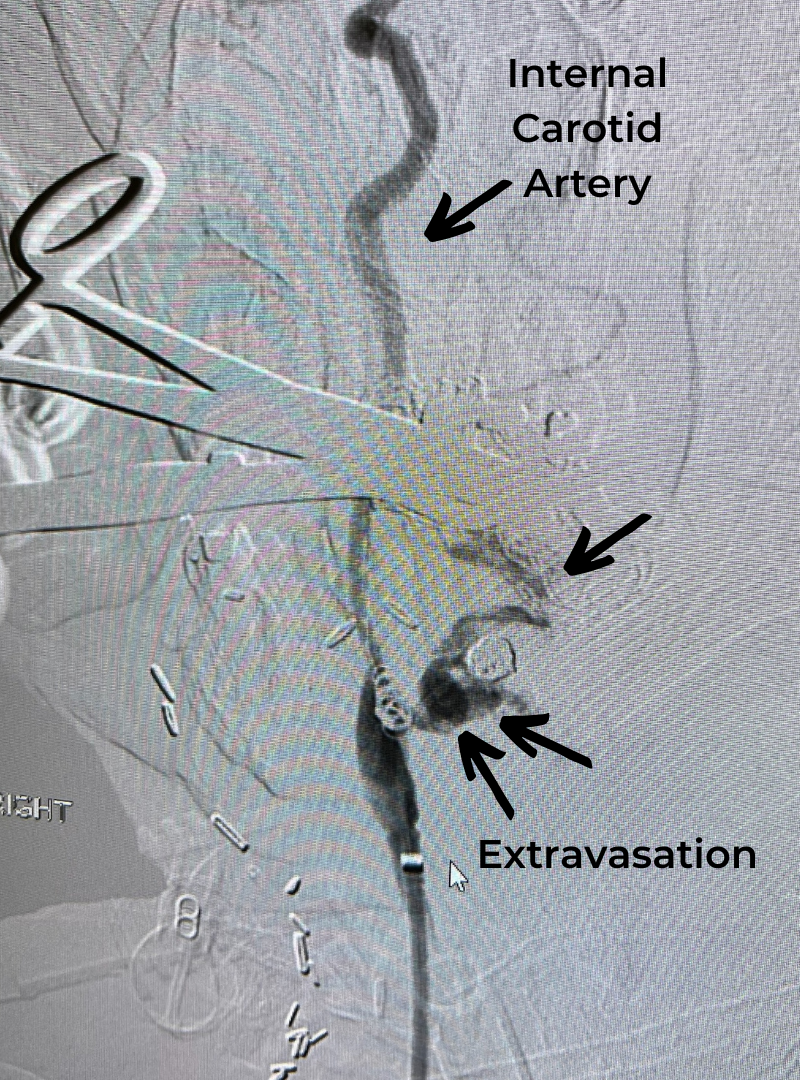

This patient is a 65-year-old man who presented to the ER after a fall from a horse. He was unable to move his arms but had some minimal movement in his legs. He had suffered a spinal cord injury affecting the cervical spinal cord and needed neurosurgical consultation.

This patient was suffering from compression of the cervical spinal cord. The fall caused an acute herniation of the cervical disc, which caused pressure on the spinal cord.

This particular spinal cord injury is called Central Cord Syndrome. This type of spinal cord injury typically affects the hands more than the legs and requires urgent surgical attention.